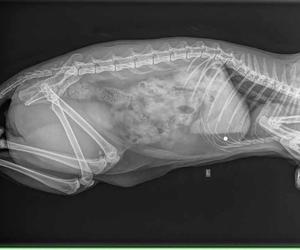

Właścicielka z kotem natychmiast pojechała do weterynarza. Smutną prawdę u weterynarza wykazało prześwietlenie RTG. Okazała się, że kotek został postrzelony śrutem z wiatrówki. Sadysta trafił w go w brzuszek.

Śrut utkwił w jamie brzusznej, ale na szczęście z boku. – Śrut mógł przecież uszkodzić jakiś organ i kot padłby. Nie rozumiem komu przeszkadzają koty – pisze nasza czytelniczka.